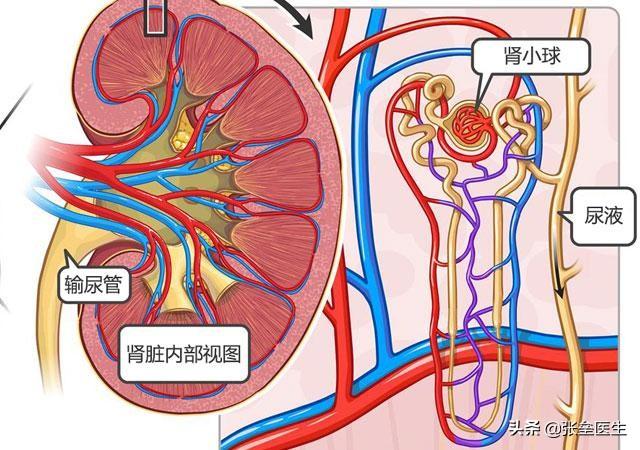

Examinons tout d'abord le lien entre les niveaux de potassium dans le sang et les reins

Je me souviens que mon professeur avait mentionné à l'école que le potassium présent dans notre corps estManger plus pour éliminer, manger moins pour éliminer, ne pas manger non plus pour éliminerNos reins sont des organes importants pour la régulation du métabolisme du potassium. Les reins sont des organes importants dans la régulation du métabolisme du potassium. 80 % du potassium est excrété par les reins et environ 10 % par les fèces et la sueur. Dans notre corps, le potassium est librement filtré à travers le glomérule, puis réabsorbé en grandes quantités dans les tubules proximaux et le segment épais de la branche ascendante de l'anse médullaire. L'excrétion du potassium dépend presque entièrement de l'action sécrétoire des tubules distaux et des canaux collecteurs.10 à 20 % du potassium filtré par le glomérule est excrété dans l'urine, dont la plus grande partie est réabsorbée dans le tubule proximal, tout comme la plus grande partie du potassium de notre urine est excrétée par le tubule distal.